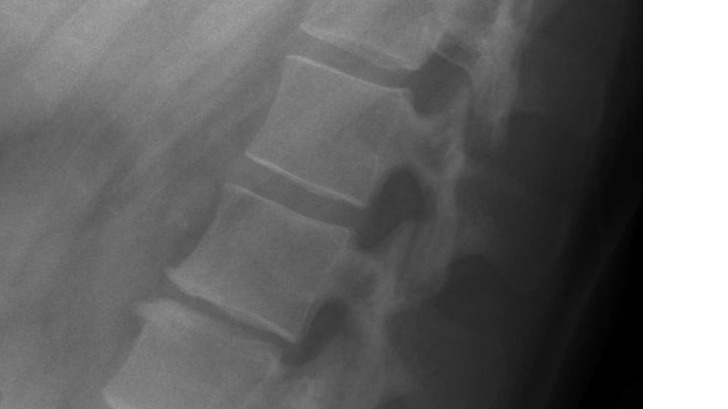

Hello my name is Krista Bain When I was a teenager I was in a incident where I came of a sprinting horse. The horse flwe me in the air and I landed crash down on my back with a 'crunch' sound in my spine. I felt tingling in my legs and adrenaline kicking in. I was so afraid. I was in shock unable to get up or move. I waited what felt to hours pass by and managed to slowly grasp myself to a stand. When I arrived back to to the horse stable I told the people there what happened. They comforted me and let me call my caregiver( I will not make the person to there discression)They knew the horse I was riding was not tame as did I but I regretfully chose to ride this horse regardless.I was instructed to go to hospital and tell my caregiver to take me there.The drive was around 45 mins from home and longer to the hospital Because I had come off horses many many times in the past my caregiver decided to make the decision not to take me to the hospital to be examined. I was in alot of pain stopped riding and took weeks off school. Because of this eventually my caregiver took me to a medical centre but when I spoke she downplayed what I said out of embarrassment of not providing my care at the time and I left that appointment deviated and without any Acc claim or examination. I have finally received a doctor after many attempts for x-rays that went unnoticed be ause I didn't receive a claim to begin with. The x-ray shows L2 &L1 fractures that have healed and a concaved scelrosis of the lower spine. The pain has only gotten worse over the years and without nerve pain killers 5 times per day I'm in absolute agony. I am afraid to take these pills for the rest of my life. I am unable to receive any help for surgery from Acc because this is a past incident. I have not been able to keep any work because my pain get heightened with any form of physical work. I am afraid of ending up in a wheelchair when I am older and having to take nerve painkillers for the rest of my life. I have a six year old son and I really cannot bare the thought of the future going downhill like this. I am afraid of being stick for the rest of my life due to the neglect of my caregiver. I have big dream to accomplish I have a great voice, I was a champion at netball and I love animals horseriding and travel. I feel down and out and the pain is closing off my ability to speak up and to get out and do things I would usually enjoy. I want to be a great role model for my son and work a great deal and provide the life for myself and my son so he can have a good future as well. I need to raise $21,000 for a lower spinal infusion surgery to be able to get this done. I would greatly appreciate any help and I thankyou ? Krista